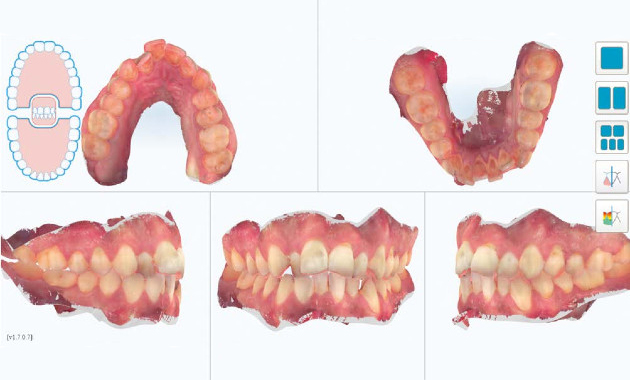

Un patient de 30 ans vient au cabinet pour un encombrement de sa zone antérieure tant maxillaire que mandibulaire. À l’examen clinique, hormis sa DDM, il était en classe 1 molaire des deux côtés, facilitant la prise de décision dans son plan de traitement (Fig.1 à 4).

Suites aux examens, nous avons réalisé un premier ClinCheck permettant d’avoir un premier repositionnement (Fig.5). On peut ici constater :

– une série de 17 aligneurs,

– une série de réductions inter-proximales maxillaires (RIP) pour un total de 1,0 mm réparties entre les 15 et 25,

– une série de réductions inter-proximales mandibulaires (RIP) pour un total de 0,8 mm réparties entre les 15 et 25,

–des taquets répartis sur toutes les dents maxillaires pour optimiser les mouvements voulus,

– des taquets sur quelques dents maxillaires.

La durée du traitement est de 34 semaines avec un changement des aligneurs toutes les 2 semaines (Fig.5 à 7).